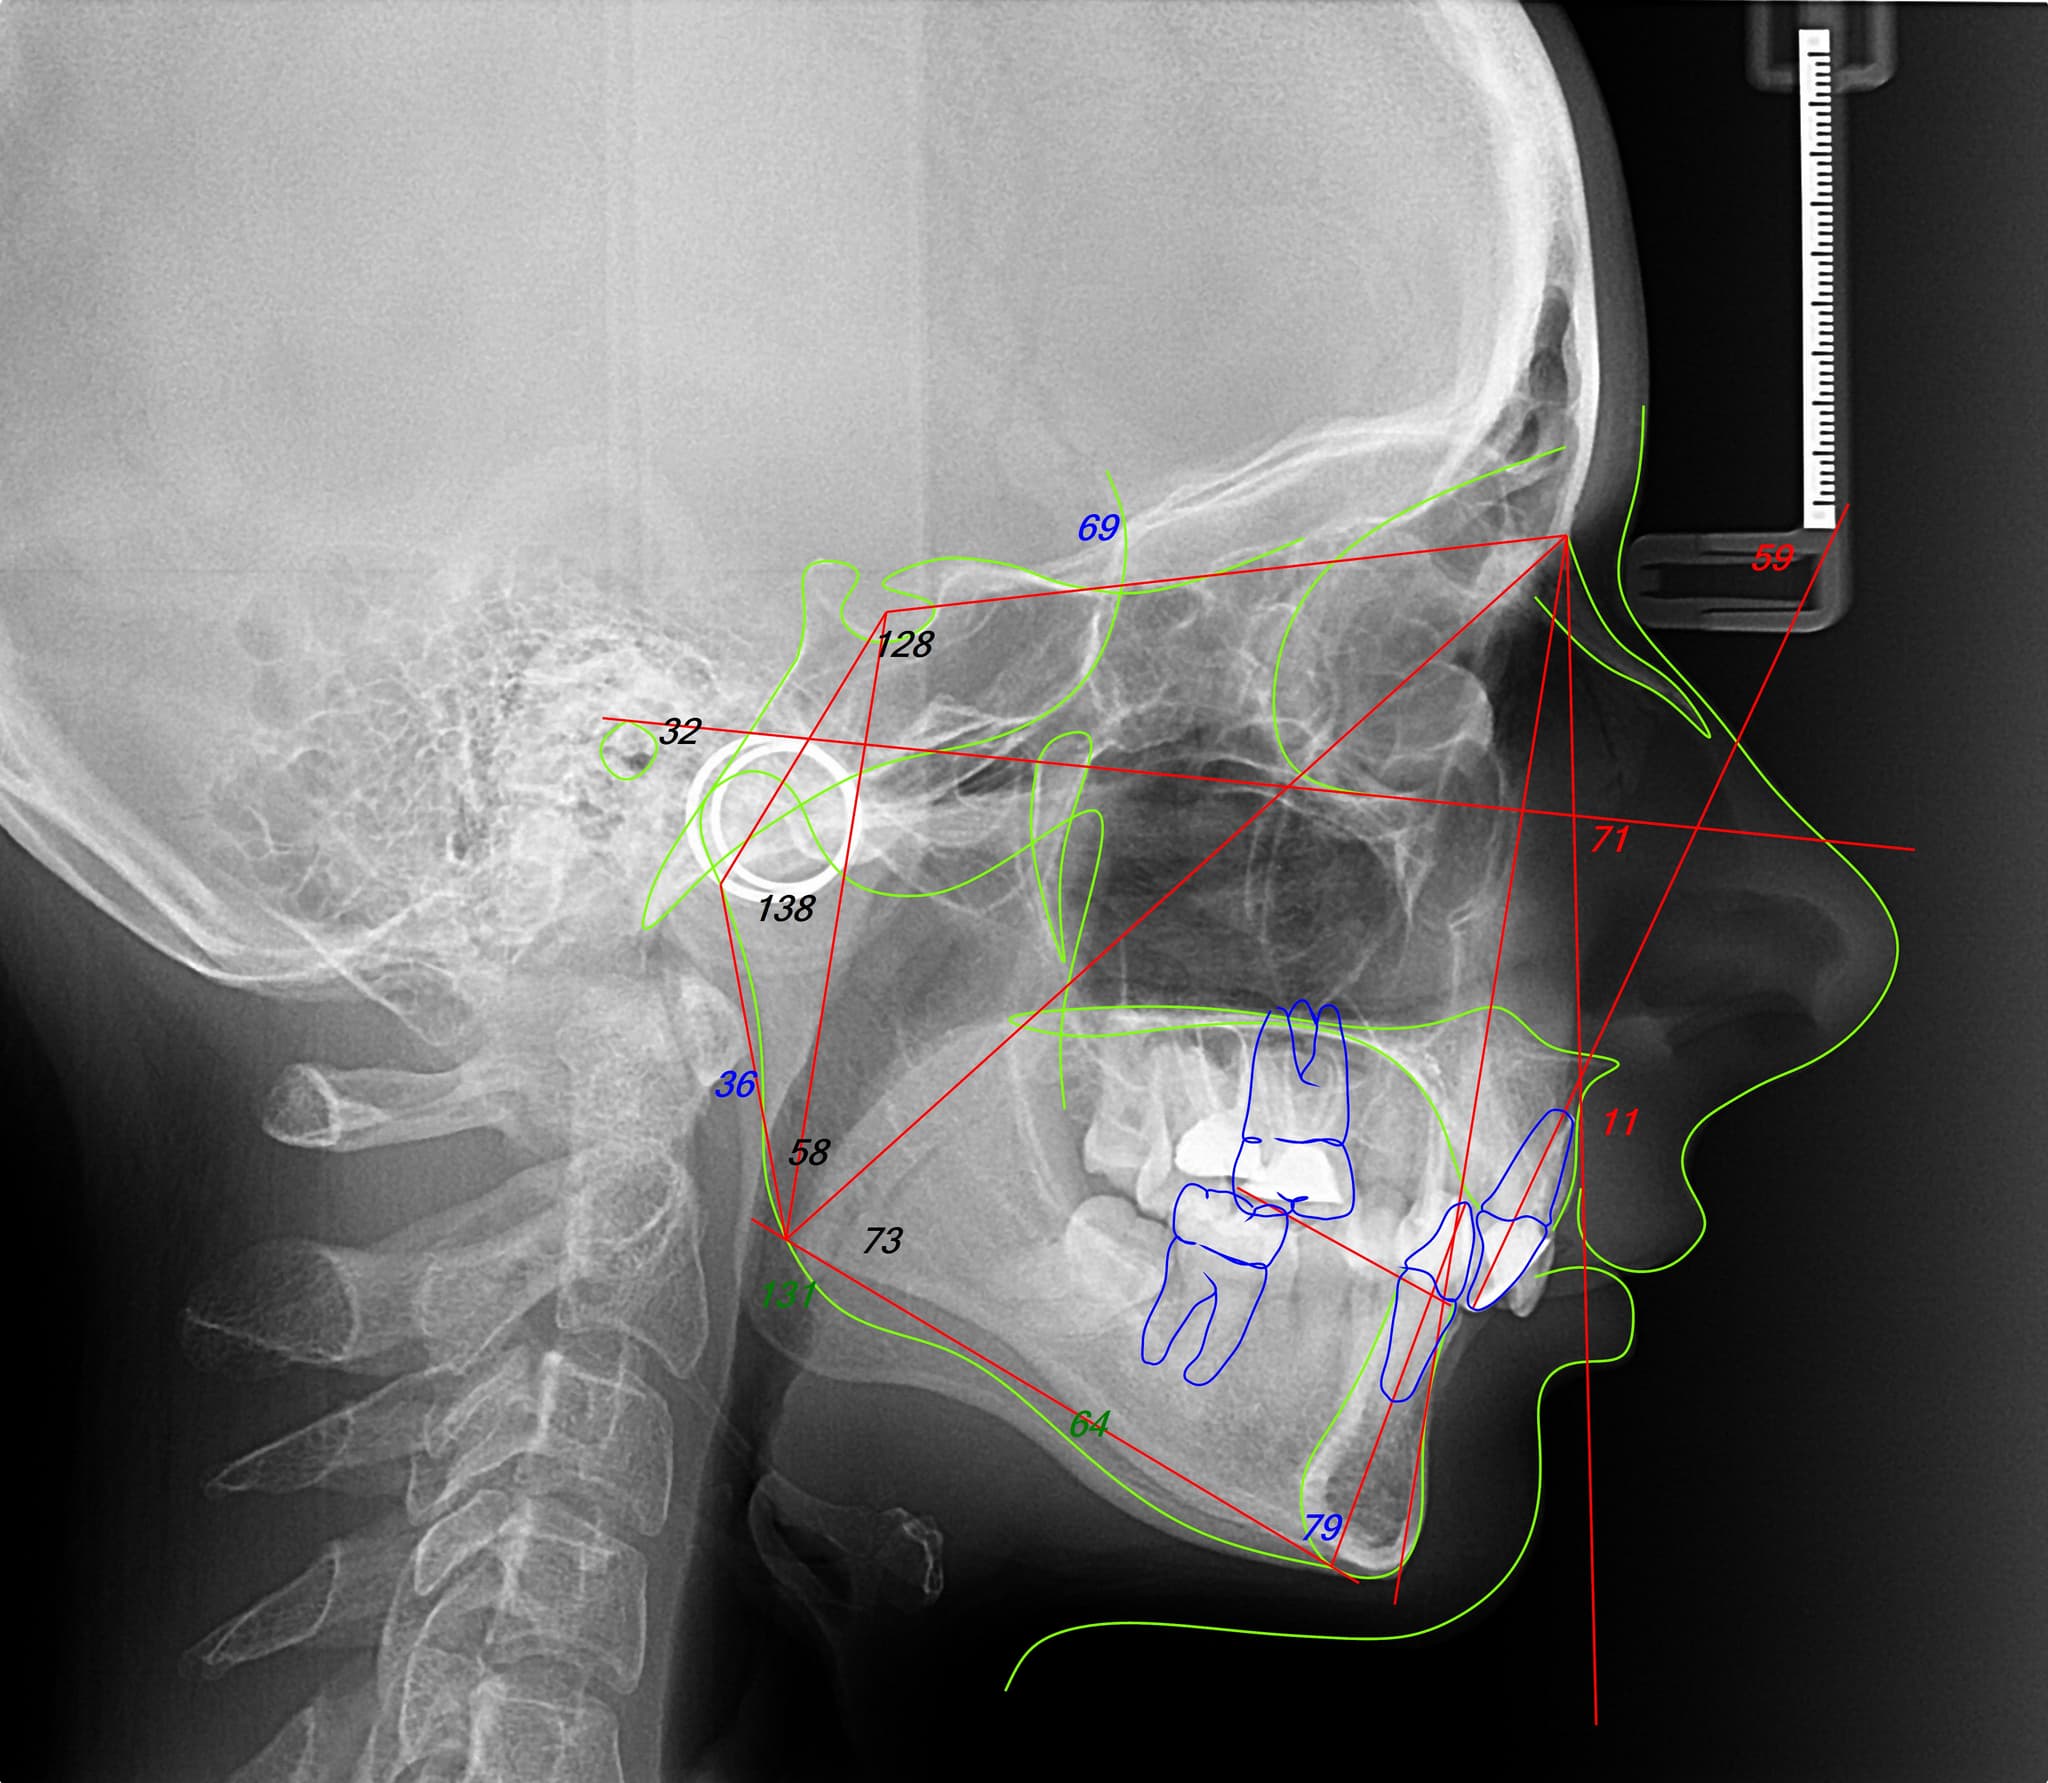

1. Diagnostic and Planning

Design before movement.

Each orthodontic case begins with a complete digital analysis: facial photos, bite scans, and jaw position. From there, we build a single interdisciplinary plan, aligning orthodontics with the broader treatment goals—be it prosthetic, surgical, or periodontal. This layered but unified approach ensures that every movement serves a long-term, integrated outcome.

Designed Around the Face

Facially driven planning.

We never treat teeth in isolation. Your facial structure, expressions, and muscle dynamics shape the entire orthodontic plan. This allows us to move teeth with intention, aiming for harmony instead of mechanical perfection.